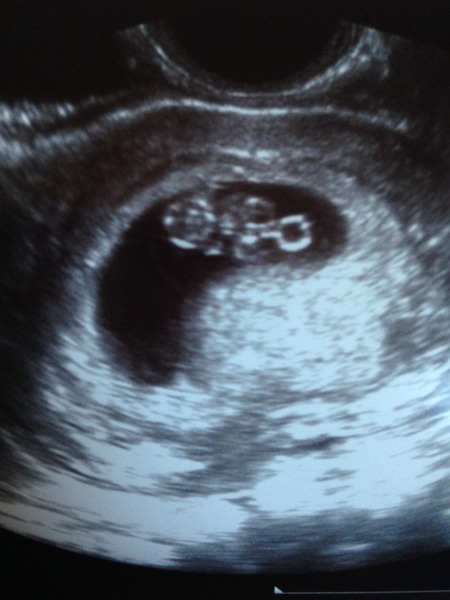

OwlinaTree · 22/12/2015 20:42

Congrats carna it really looks like a baby, wow!

AlfieTheRailwayCat · 22/12/2015 21:01

carna congrats!

My bean has a heartbeat, I'm 7+1 which is exactly what I thought and its 1.02cm. So pleased! It had a nice yolk sac too.

Mine was a private early scan so I could have as many pictures as I wanted really. The screen was great made it so clear. The sonographer was really helpful and answered my questions, checked all round my uterus and ovaries and focused on the heart beat a few time for me. It was lovely and reassuring. Obviously it's never a guarantee but it has made me feel a little more settled.

carnassials · 23/12/2015 10:29

My 8 week scan was part of the NHS IVF process, so it was booked in from the day I found out.

Glad all the scan went well ladies. The pictures are fab!